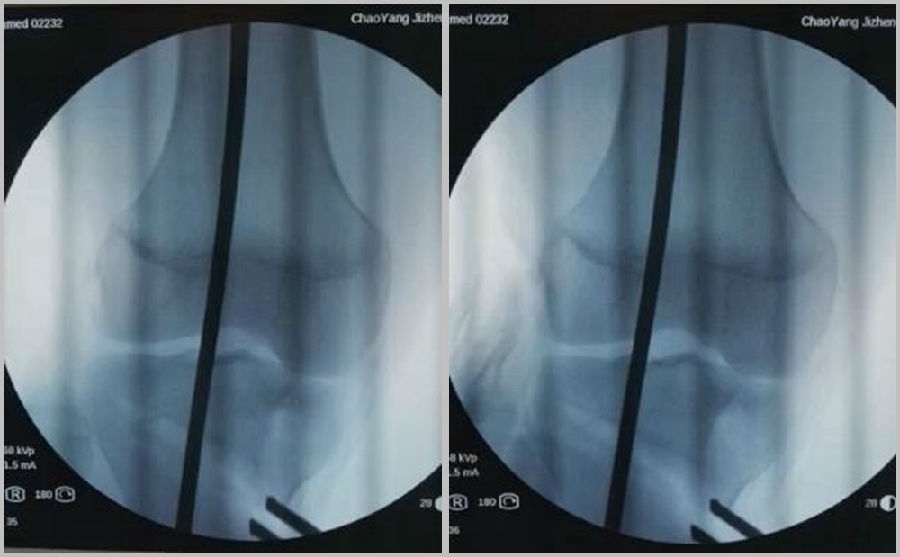

1、综合判断力线的方法

现在对于力线的判断大致通过以下几方面:①大体形态;②透视确定力线,连接股骨头中心、踝关节中心,看力线杆和膝关节中心的位置关系;③MPTA(胫骨平台关节线和胫骨侧机械轴夹角);④PSI。

(3)力线验证未模仿负重应力

现在所谓的目标力线应该是模仿负重时的力线。做截骨时,通常会将力线轻度外移,如果没有考虑关节内畸形、韧带松弛或是软骨磨损,那么在负重时,在内侧副韧带撑开过程中,会出现力线偏移。所以要注意,手术中间在调整目标力线时,要以应力状态下为标准。